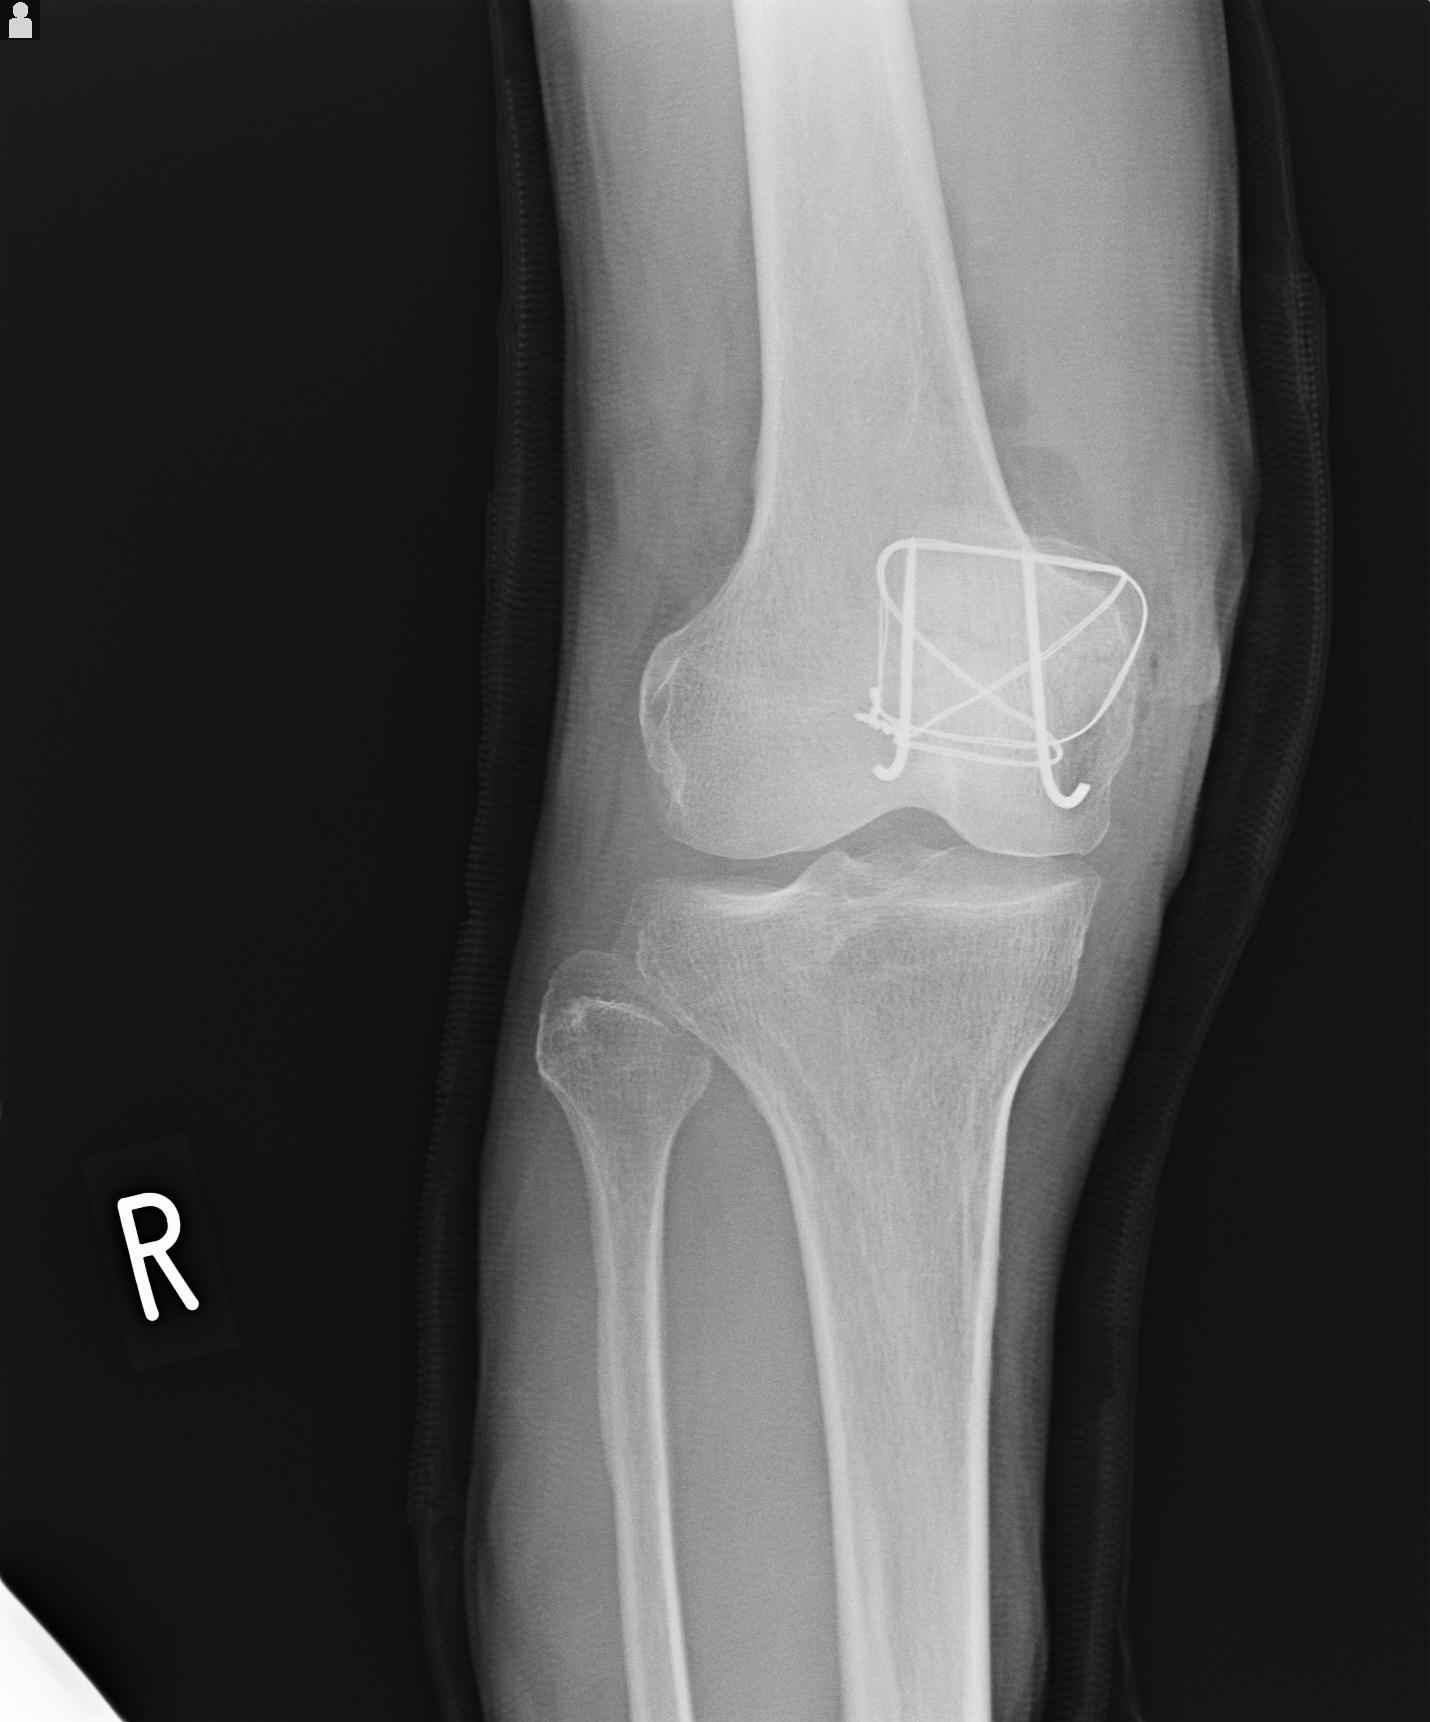

49554 3/13 膝 4R 3/16 4R 1/18 2R 78歳男性 膝蓋骨骨折